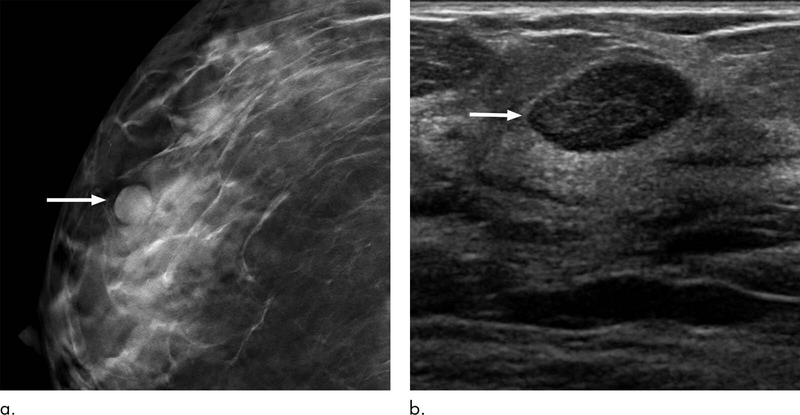

Birads là một công cụ đánh giá rủi ro và đảm bảo chất lượng được phát triển bởi Trường Cao đẳng X quang Hoa Kỳ, cung cấp từ vựng và sơ đồ báo cáo được chấp nhận rộng rãi về hình ảnh vú. Nó áp dụng cho chụp nhũ ảnh, siêu âm và MRI. Bài viết này sẽ giúp bạn hiểu rõ hơn về Birads và ý nghĩa của chúng đối với sức khỏe của bạn.

Birads (Hệ thống dữ liệu và báo cáo hình ảnh vú) là một hệ thống tính điểm bằng số được sử dụng để đánh giá nguy cơ ung thư vú dựa trên báo cáo chụp quang tuyến vú, siêu âm vú hoặc chụp ảnh cộng hưởng từ vú (MRI).

Chụp quang tuyến vú là một xét nghiệm chụp ảnh X-quang để kiểm tra sức khỏe vú. Đây là công cụ hiệu quả nhất giúp phát hiện ung thư vú, đặc biệt là ở giai đoạn sớm nhất. Nó cũng có thể được sử dụng như một công cụ theo dõi khi bác sĩ phát hiện khối u bất thường trong quá trình khám lâm sàng vú. Những bất thường đó có thể chỉ ra sự hiện diện của bệnh ung thư hoặc các khối và cấu trúc lành tính, không gây ung thư.

Trường Cao đẳng X quang Hoa Kỳ đã thiết lập một hệ thống báo cáo được tiêu chuẩn hóa, được gọi là Hệ thống Dữ liệu và Báo cáo Hình ảnh Vú (Birads), để mô tả các phát hiện và kết quả hình ảnh vú trên chụp nhũ ảnh, siêu âm và MRI. Khái niệm Birads lần đầu tiên được phát triển cho chụp nhũ ảnh vào đầu những năm 1990 để giải quyết các vấn đề biến đổi và thực tiễn báo cáo không rõ ràng khi việc sử dụng phương thức này ngày càng tăng.

Kể từ khi ra đời và phát triển, Birads đã trở thành trung tâm trong thực hành chẩn đoán hình ảnh vú. Một thành phần quan trọng của hệ thống báo cáo này là một danh mục đánh giá được xác định, được đánh số từ 0 đến 6 dựa trên khả năng xảy ra bệnh ác tính và khuyến nghị quản lý lâm sàng tương ứng được sử dụng với mỗi danh mục đánh giá. Việc sử dụng ngôn ngữ phổ biến này trong các báo cáo hình ảnh vú cho phép các bác sĩ X quang truyền đạt rõ ràng các kết luận chẩn đoán và khuyến nghị tới bác sĩ chính, bác sĩ phẫu thuật và bác sĩ chuyên khoa ung thư của bệnh nhân trong quá trình điều trị bệnh.